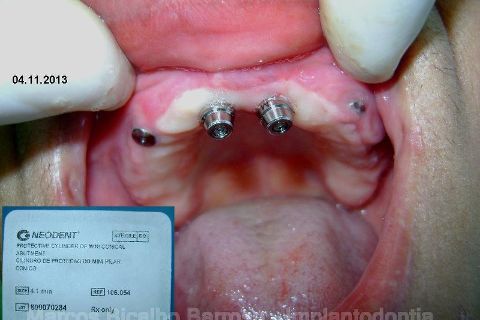

Atualização do caso clínico que já postei, "REABILITAÇÃO EM MAXILA ATRÓFICA COM IMPLANTES", um caso que inclui expansão do rebordo estreito com cinzel e martelo, expansores rosqueáveis, enxerto e instalação dos implantes distais inclinados tangenciando seio maxilar. Inclui esvaziamento do forame nasopalatino e preenchimento com biomaterial para instalação de dois implantes próximos dele. Cirurgia realizada em única sessão, com instalação dos 6 implantes. Para os colegas que não conheceram e/ou esqueceram da apresentação, este é o resumo do caso na fase cirúrgica.http://www.youtube.com/watch?v=BtvexFexRPA&hd=1

FASE PROTÉTICA DA REABILITAÇÃO EM MAXILA ATRÓFICA...incluindo a reabertura, instalação dos minipilares e PTR provisória reembasada sobre os cilindros de proteção.